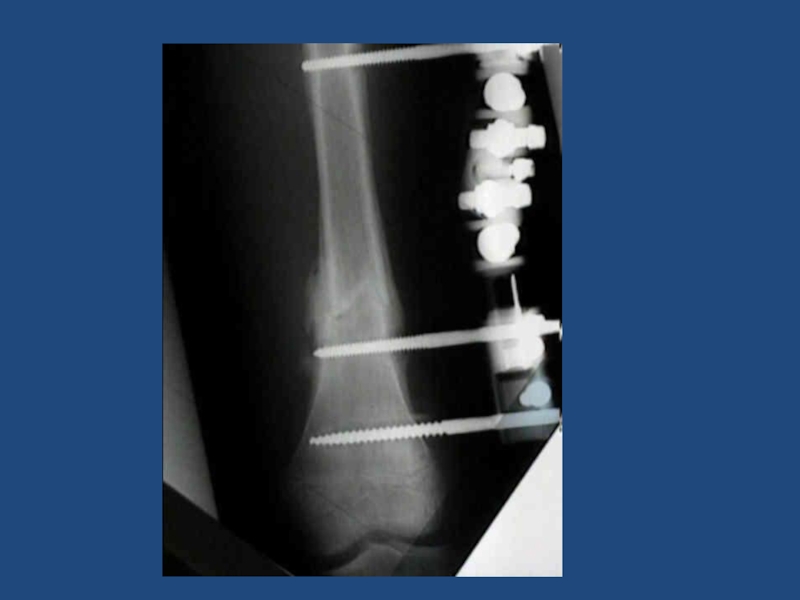

Сросшийся перелом с/3 бедра, внутрикостный центромедулярный блокирующий остеосинтез

28Сросшийся перелом с/3 бедра, внутрикостный центромедулярный блокирующий остеосинтез